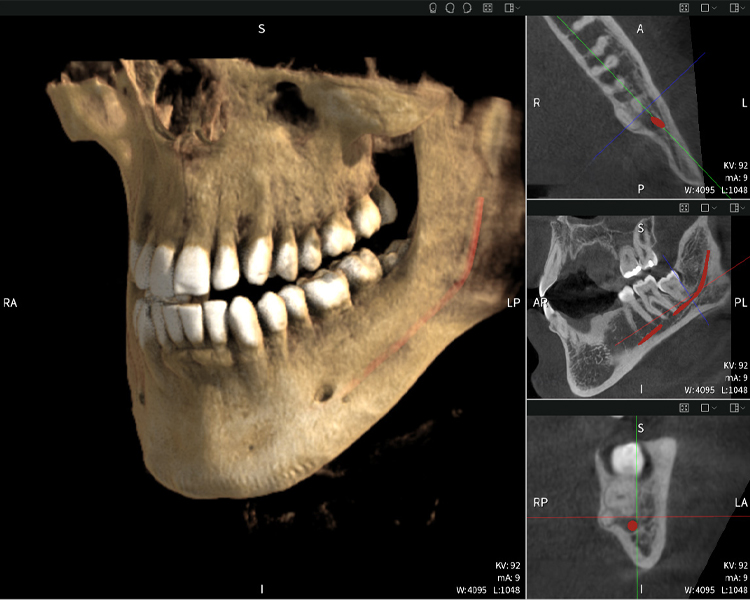

Figura b: Resultados de imagen de Seethrough Max, sobre un fondo negro.

Figura b

Las figuras b–d muestran varias vistas de una reconstrucción 3D de la mandíbula, proporcionando una visión general completa de la anatomía mandibular, la posición de los nervios en relación con los dientes y permitiendo evaluar la simetría y alineación dentaria.